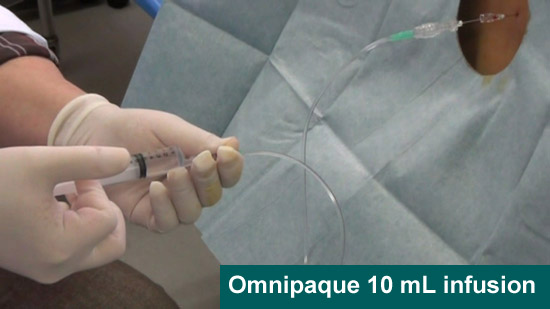

●Contrast medium

Omnipaque for computed tomography (CT) 10 mL

(8)Omnipaque 10 mL infusion